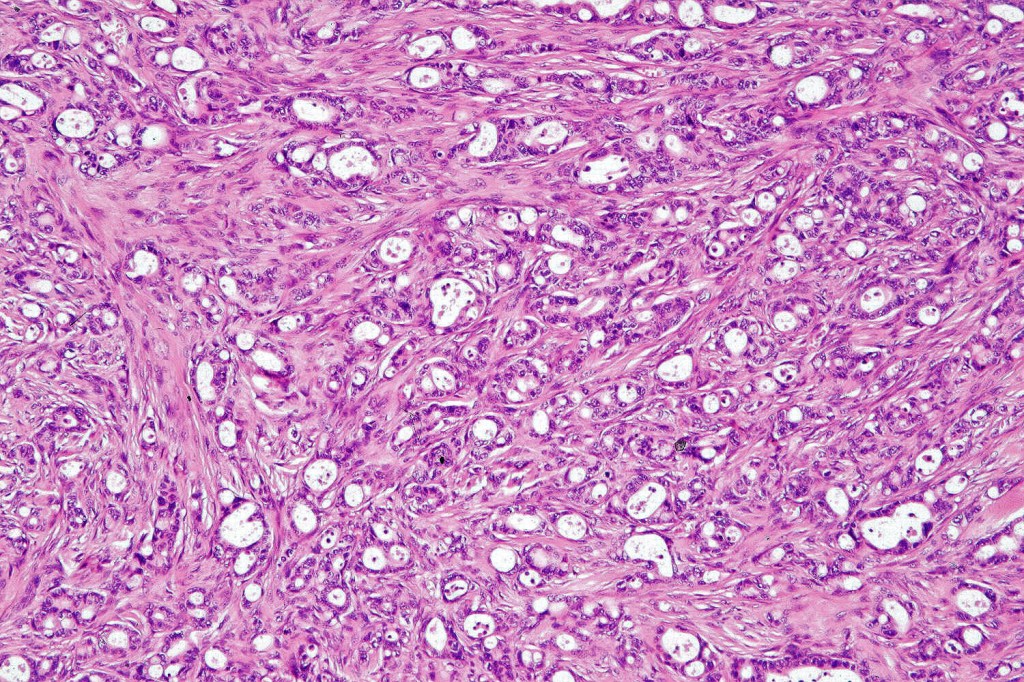

Histological features

Dermal tumor +/- subcutaneous fat

•Nests & cords of epithelial cells showing ductal differentiation/intracytoplasmic lumina embedded in a dense fibrous stroma

•Eosinophilic cytoplasm & irregular vesicular nuclei with small nucleoli

•Variable pleomorphism & mitoses

•Perineural infiltration & lymphovascular invasion commonly present